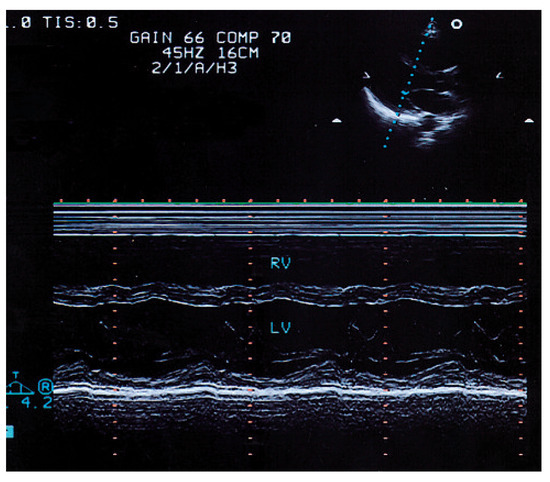

Summary. We report two cases of a 83- and a 78-year-old female with tetralogy of Fallot (TOF) who underwent operation at an advanced age in their 30’s, making them the oldest patients repaired for tetralogy of Fallot [...]